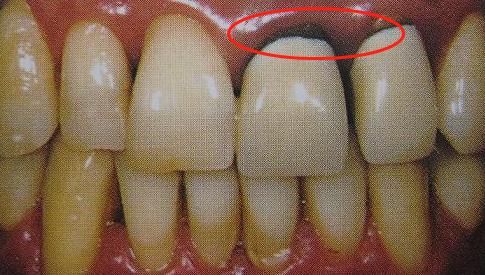

2、烤瓷牙内部结构

真牙的釉质和内层的牙本质都有一定的透光性,由于烤瓷牙内部的金属层是不透光的,光线在烤瓷牙的内部折射时便不能很好的到达烤瓷牙颈部,因此烤瓷牙和牙龈接触的部位相对其他部位发暗。这种发黑现象是所有金属烤瓷牙的通病。

因为烤瓷牙制备不合格,烤瓷牙和真牙不够密合,包括贵金属烤瓷牙(黄金烤瓷牙)在内,无论采用那种金属都可能出现牙龈黑线。